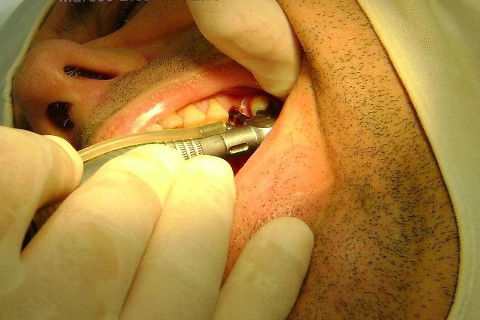

Instalação de um implante em região do 26. Utilizamos um implante cone morse Alvim Neodent 4.3 X 11,5. Foi uma cirurgia muito rápída e minimamente traumática, sem retalho e sutura.